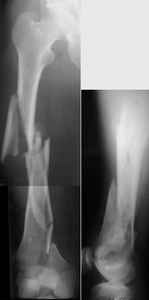

I presented a series of ~25 such cases at EuroTrauma'2004. Many cases were discussed here. I attach am example. Look also recent cases at http://www.hwbf.org/hwb/conf/alex58/scfx.htm,

http://www.hwbf.org/hwb/conf/alex63/alex63.htm

I do realize that you are master surgeon, and congratulations on another excellent, spectacular case (result), but,

- Your last posted case: how is possible to have secure fixation with applied construct without additional casting, bracing or Ilizarov?

THX, initial images are

1,

2.

At that moment we had in stock only the 10 mm solid nails so of course there was no idea about early weight bearing. But it was quite enough for early knee ROM excersises (see attached). Two locking screws through the distal block provided that.